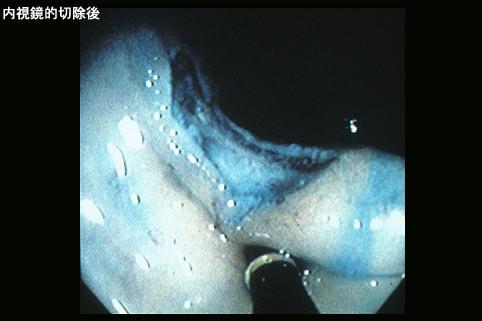

Caso TIC(Conferencia TeleImágen de varios puntos del Tubo Digestivo en conjunto)

2005/05/17 |

femenino |

50-54

1995-1999's case |